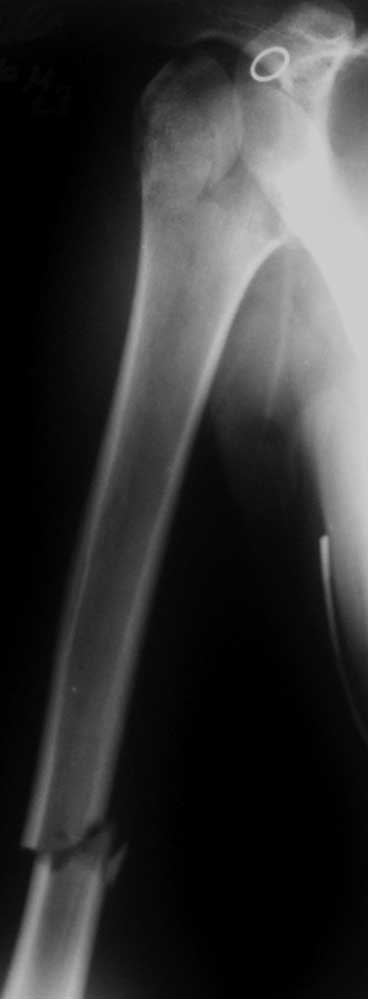

Женщина 23 лет получила травму в результате ДТП (пассажир). Поступила в отделение 07.06.2012 (травма в день поступления).

Диагноз: закрытый перелом шейки правого плеча с отрывом большого бугорка, закрытый поперечный оскольчатый перелом правого плеча на границе средней и нижней трети.При поступлении конечность иммобилизирована задней гипсовой лонгетой от надплечья до головок пястных костей.

Вложение не в текстовом формате было извлечено…

Имя     : 1.JPG

Тип     : image/jpg

Размер  : 24852 байтов

Описание: отсутствует

Url     : http://weborto.net:8080/pipermail/ortho/attachments/20120609/f6e7d42f/attachment-0004.jpg